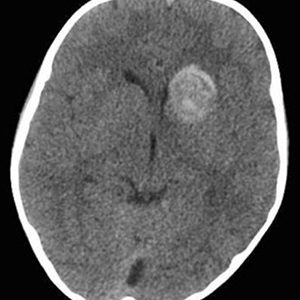

Noviembre 2025. Hospital Italiano

Paciente de 4 años. TEC, Vómitos.